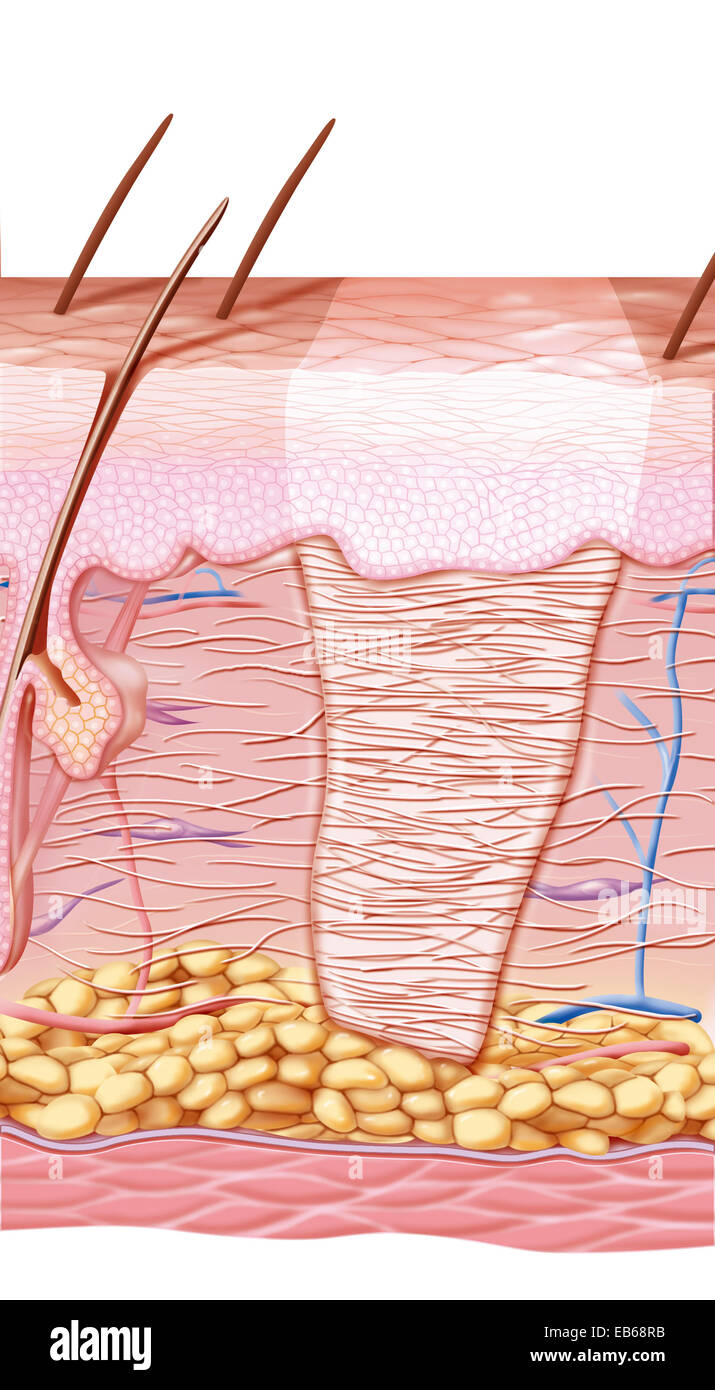

SCAR DRAWING Stock Photohttps://www.alamy.com/image-license-details/?v=1https://www.alamy.com/stock-photo-scar-drawing-75741327.html

SCAR DRAWING Stock Photohttps://www.alamy.com/image-license-details/?v=1https://www.alamy.com/stock-photo-scar-drawing-75741327.htmlRMEB68RB–SCAR DRAWING